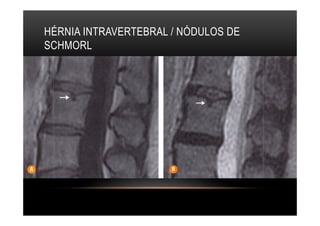

HÉRNIA INTRAVERTEBRAL / NÓDULOS DE

SCHMORL

•  Hérnia Intravertebral / Nódulos de Schmorl são hérnias discais se insinuam em

direção cranio-caudal para os platôs vertebrais. O tecido herniado forma um defeito

na superfície da vértebra, geralmente em localização central ou posterior, e, em

alguns casos de herniações agudas e sintomáticas, ocorrem alterações reativas na

medular óssea com hipersinal em T2 em torno da área de herniação.